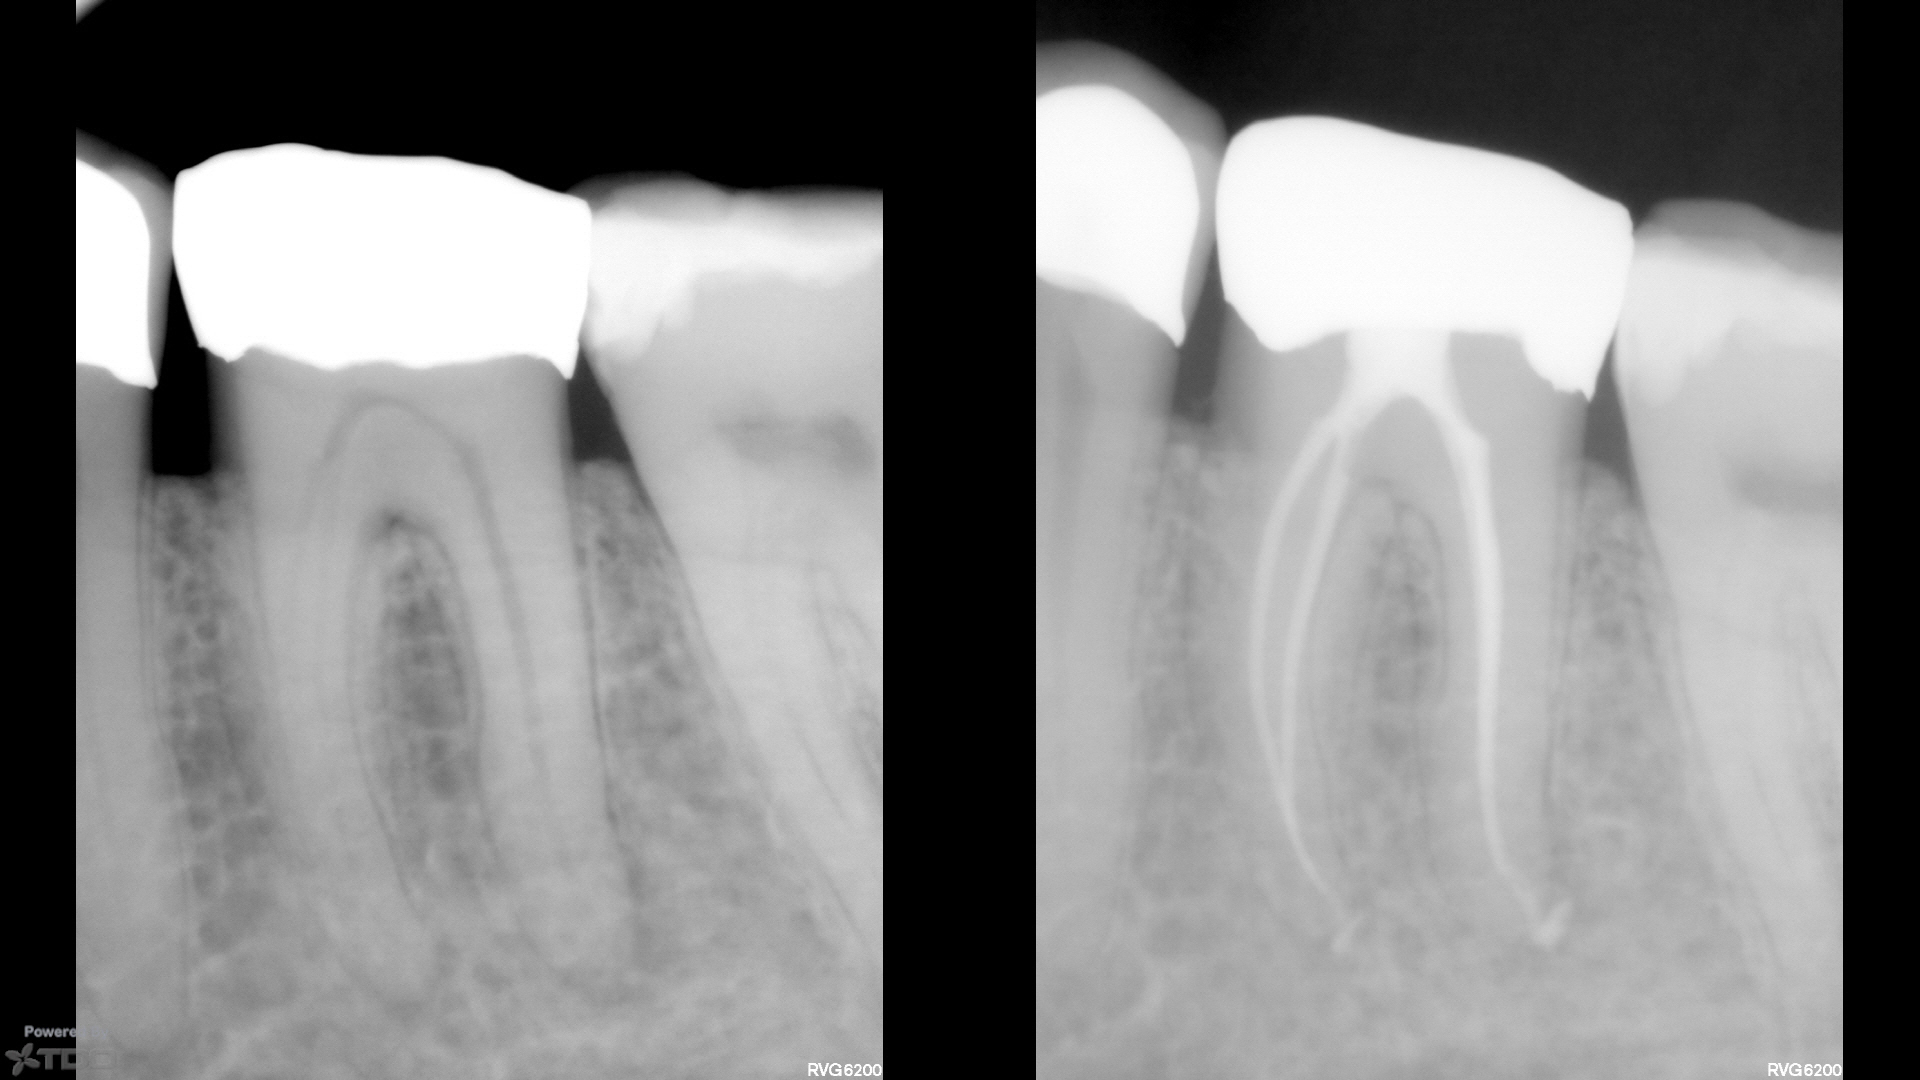

Here are a couple of single-cone BC sealer cases from today, and last week.

Both are SSW 17/V.04, single-cone (#20 cone…very thin and flimsy).

No downpack, no backfill.

CBCT post-op on the one from today demonstrating some apical anatomy if that tickles your fancy.

The second one from last week was a one-step.